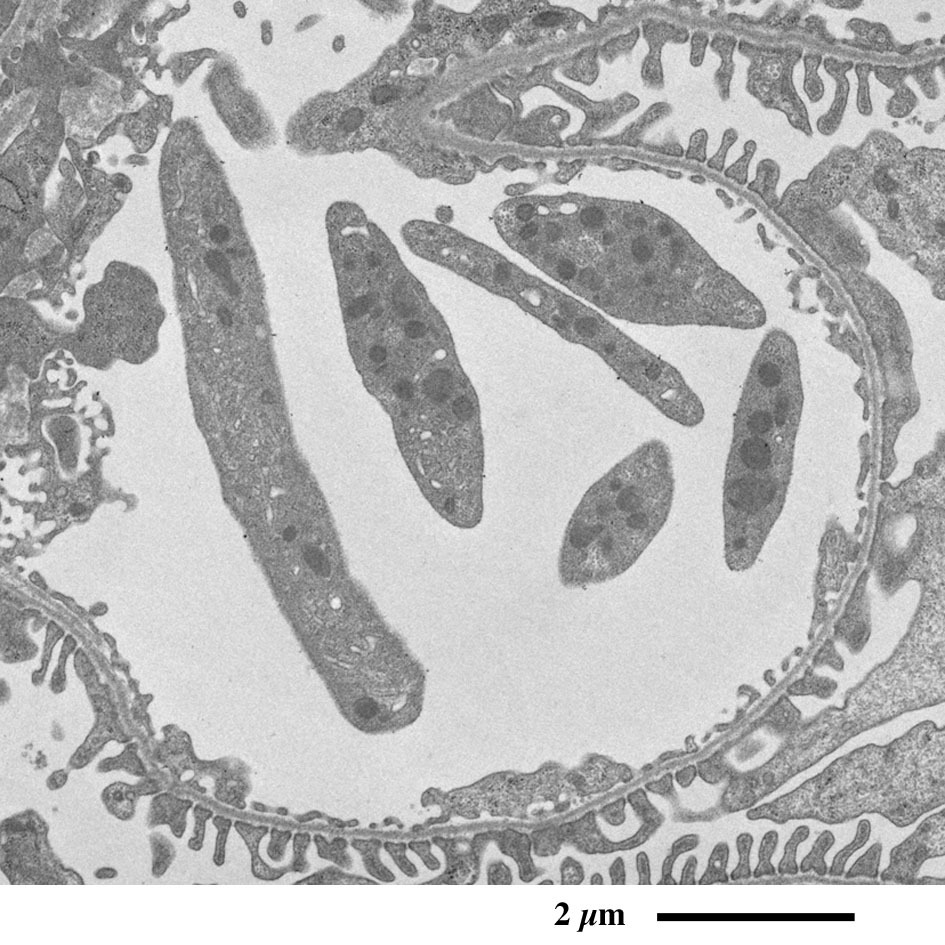

【 超薄切片の透過型電子顕微鏡画像 】

Transmission electron microscopic image of ultrathin section

近位尿細管上皮細胞

原尿に含まれるグルコースや電解質、水など身体に必要な物質を再吸収するため、

上皮細胞の頂上部に微絨毛が並んで表面積を増大しています。

黄:尿細管腔、青:尿細管上皮細胞、赤:毛細血管